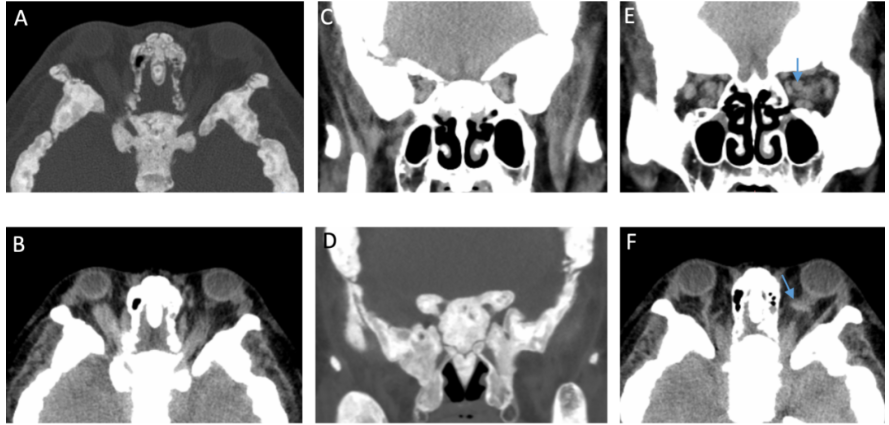

Ophthalmic examinations revealed mild visual field defects and thinning of the retinal nerve fibre layer. Crucially, orbital CT scans showed the root cause: diffusely thickened orbital bone walls, severe narrowing at the orbital apex, and constricted optic canals. These structural changes (indicated by blue arrows in the accompanying image) were compressing the optic nerves. Additionally, dilated superior ophthalmic veins suggested impaired blood flow, likely increasing orbital pressure and further compromising optic nerve function.